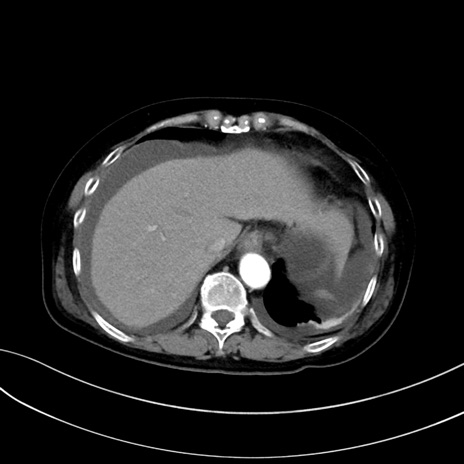

(冠状断像)1日半後